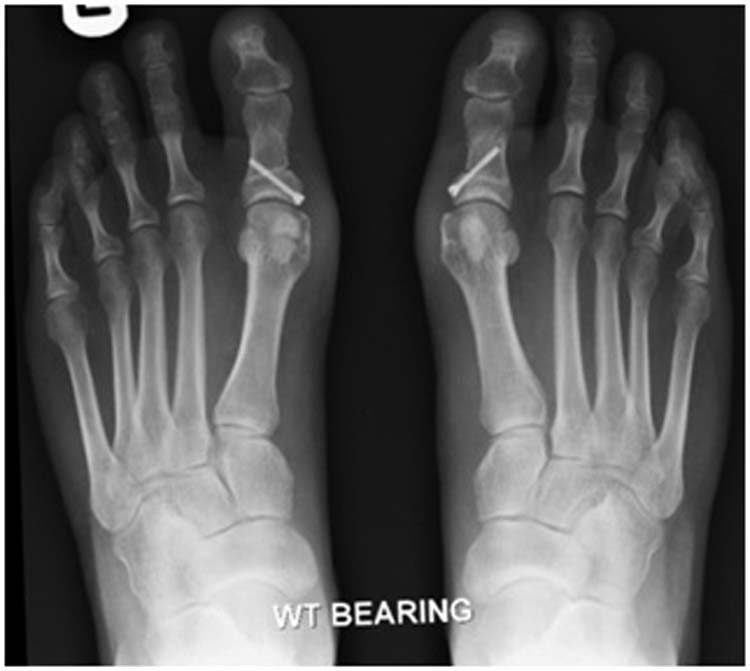

Double Scarf Akin Osteotomy (Bilateral Bunionectomy) Fixing my Feet 2014 What Is A Scarf And Akin Osteotomy A scarf osteotomy (often performed alongside an akin osteotomy), is one of the most popular types of bunion surgery. There are many different types of bunion operations but the operation of choice required for moderate bunion deformity is called a scarf / akin. Bunion correction with scarf and akin osteotomy. A scarf osteotomy is a type of procedure for hallux. What Is A Scarf And Akin Osteotomy.